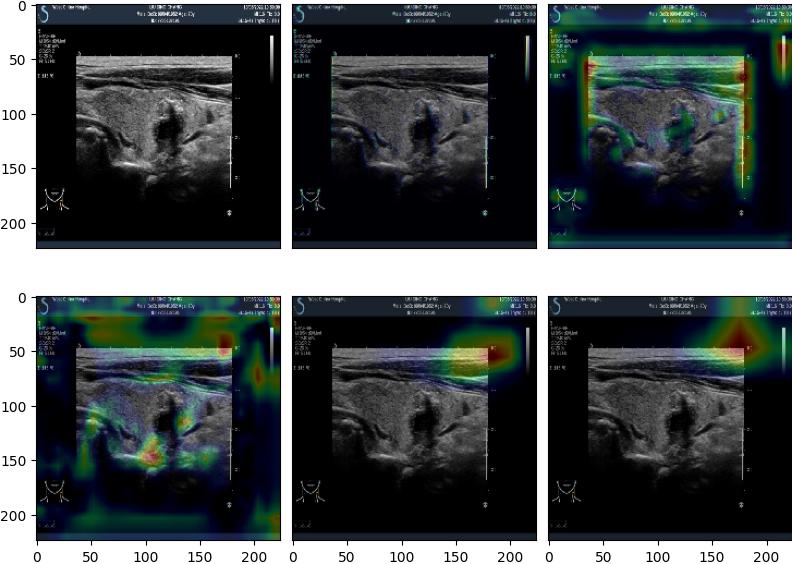

Cancer Classification from Ultrasound Image

Deep Learning Algorithm to Detect Thyroid Cancer

Examples 1

Benign

94.50%

Malignant

5.50%

Examples 2

4.00%

96.00%